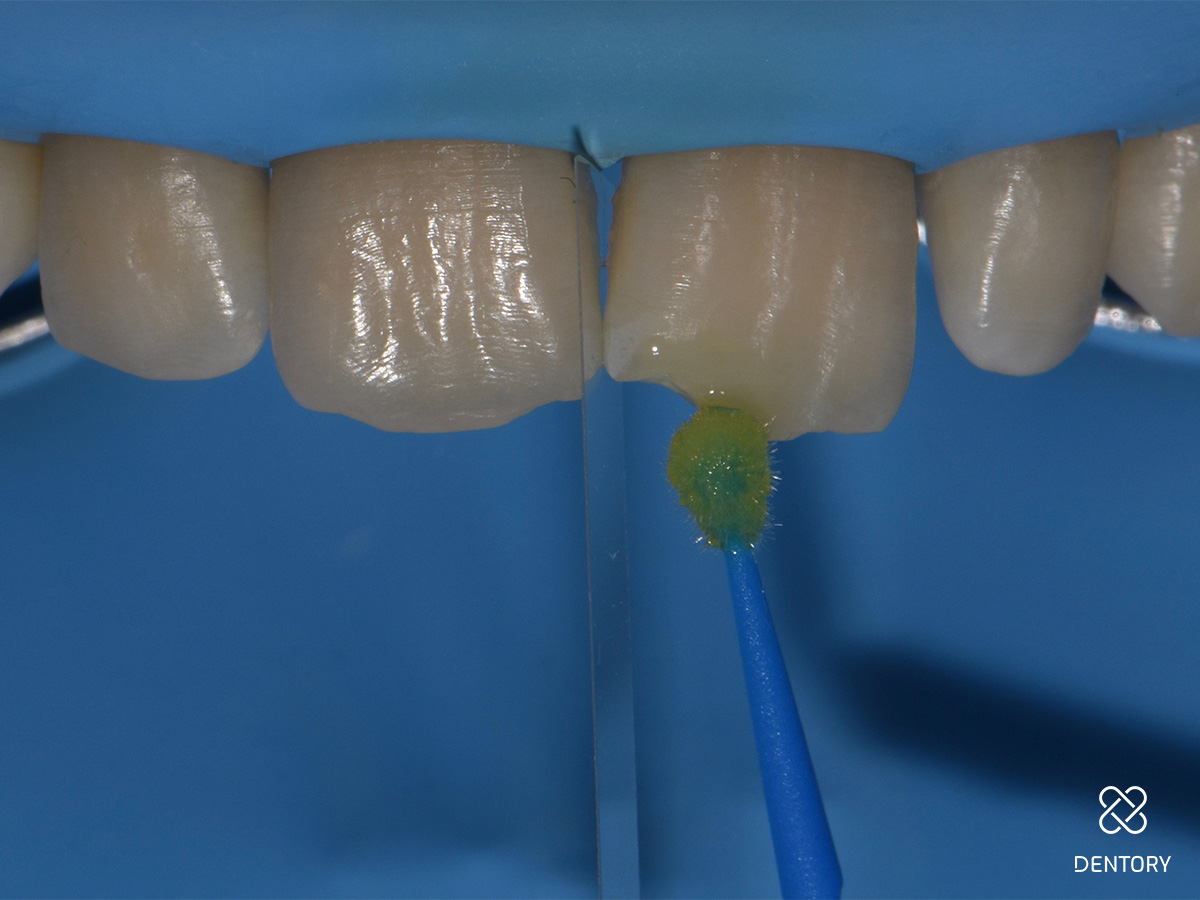

Abbildung 4

Ätzgel (37%) auftragen: Der Verlauf der Anschrägung kann anhand des Ätzgels nachvollzogen werden.